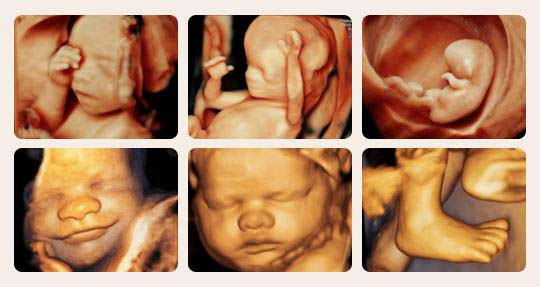

四维彩超是孕期排畸检查较为先进的一项内容,不仅可以看见宝宝在妈...

四维彩超相较于二维、三维B超而言,存在很大的优势,这些都是二维、...

随着四维彩超的问世,很多孕妈妈也不再热衷与三维彩超,四维彩超拥有...

一样的排畸,不一样的临床效果 -------美国GE E8超清四维彩超全面...